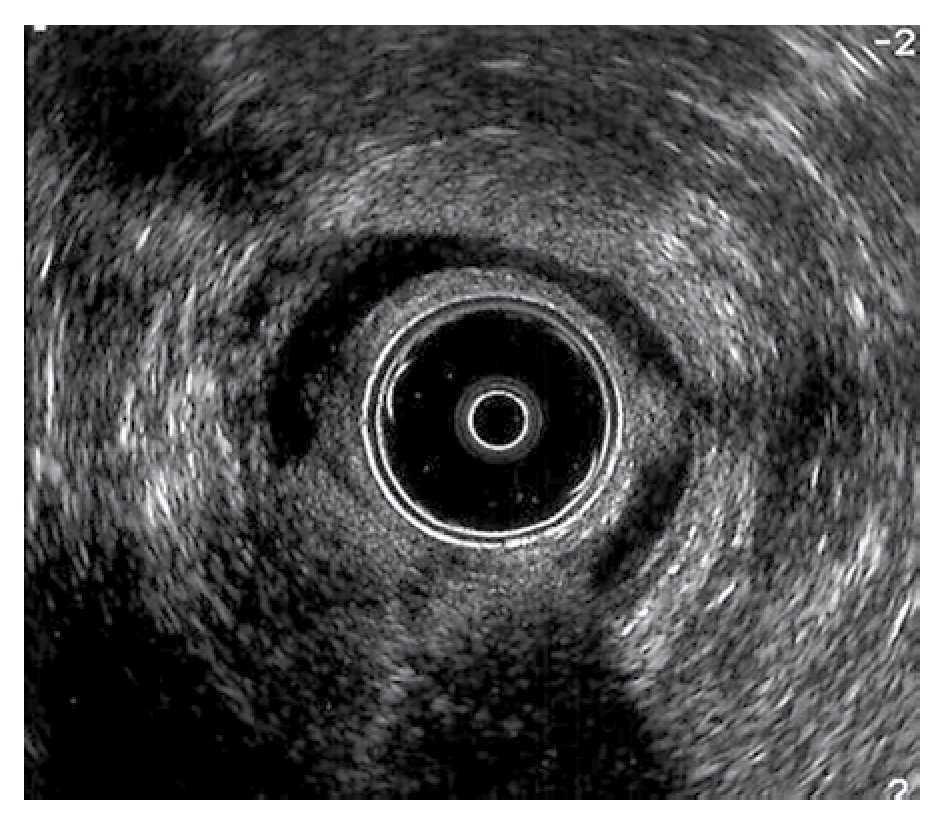

Técnica quirúrgica: Los pacientes tuvieron un lavado rectal con fosfato de sodio (Fleet enema®) una noche antes de la cirugía y una hora previa al procedimiento. Recibieron ciprofloxacino y metronidazol intravenosos previo a la intervención quirúrgica, que se realizó bajo sedación en quirófano y en decúbito lateral izquierdo, realizándose ultrasonido endoanal para identificar la lesión del esfínter interno. Después de realizar asepsia y antisepsia del área perianal con iodopovidona, se inyectaron 7.5 mL de silicón en cada paciente, con tres cartuchos de 2.5 mL cada uno (Macroplastique®), bajo guía ultrasonográfica en la zona de lesión del esfínter interno, así como en el espacio interesfintérico (Figuras 2 y 3). En total se aplicaron cuatro implantes a cada uno de los pacientes, uno en el sitio de la lesión y los otros en el espacio interesfintérico. Los procedimientos se realizaron sin complicaciones y ninguno de los pacientes presentó infección en el sitio quirúrgico.

¿ Figura 3. Dos implantes posteriores y uno lateral izquierdo colocados en el espacio inter-esfintérico y en el esfínter interno.